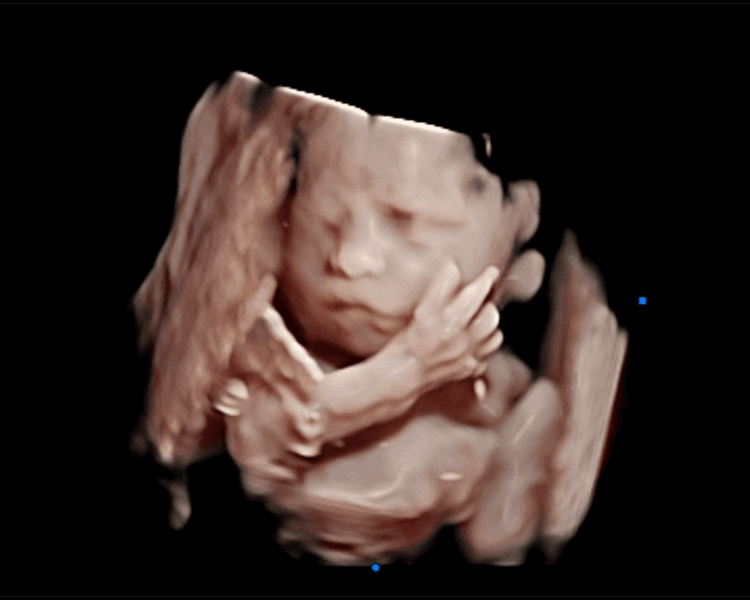

Ecografía Emocional 5D: Vive la Magia de Conocer a tu Bebé. En Ecolove ❤️, te invitamos a vivir una experiencia única y mágica con nuestra ecografía emocional 5D. Imagina ver a tu bebé en alta definición 3D y 5D, captando sus movimientos, gestos y hasta sus primeras sonrisas, todo con la calidad de una película de cine. 🎥 Es mucho más que una ecografía, es un momento lleno de amor, emoción y conexión. Un recuerdo eterno que podrás compartir con los que más quieres. 🤰🏻👨👩👦👦 ¡Reserva tu cita y deja que la magia del cine te acerque a tu bebé!